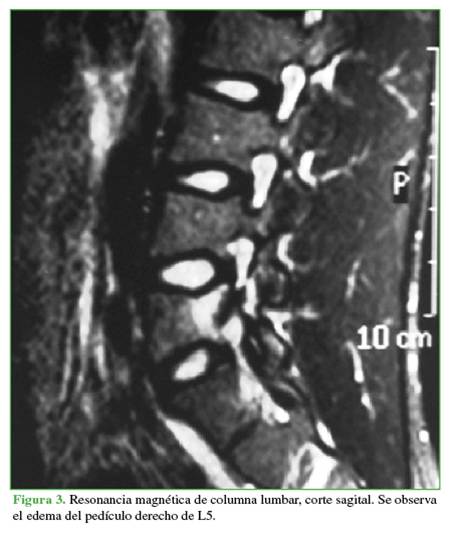

Se tomaron radiografías de columna lumbar, de frente, de perfil y oblicuas que revelaron esclerosis del pedículo derecho y espondilólisis izquierda de L5. La tomografía computarizada mostró, además de la lesión antes descrita, una solución de continuidad en el pedículo derecho, con márgenes escleróticos e hipertróficos (Figuras 1 y 2). En la resonancia magnética, se visualizó un edema en dicho pedículo lumbar (Figuras 3 y 4).

Un rasgo habitual en la pediculólisis es la esclerosis del pedículo, pero aún no resulta claro si esto representa un fenómeno de adaptación anterior a la fractura o si es una consecuencia de ella.9 Esta esclerosis unilateral le da el aspecto de vértebra anisocórica en la imagen radiológica. Sin dudas, la tomografía computarizada permite evaluar mejor el cuadro, realizar diagnósticos diferenciales, controlar la evolución y, en algunos casos, efectuar una planificación terapéutica. Las características suelen ser la presencia de solución de continuidad radiolúcida con márgenes escleróticos e hipertróficos.4 La resonancia magnética tiene una elevada sensibilidad a la hora de diagnosticar este tipo de lesiones que, si bien puede mostrar o no el trazo de fractura a nivel del pedículo, sí manifiesta el edema